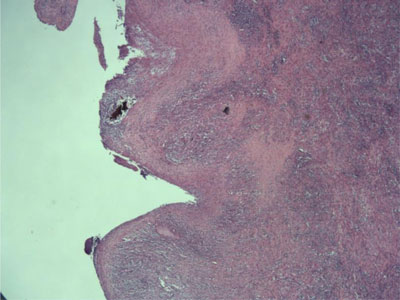

A laparoscopic resection of the diverticulum and adjacent sigmoid, with primary colonic anastomosis was performed. No postoperative complication occured and the patient was discharged on post-operative day 5. The pathology examination revealed a giant sigmoid diverticulum consisting of a fibrosclerotic wall colonized by acute and chronic inflammatory elements with a complete destruction of the endodiverticular mucosal layer and was classified type 2 according to the classification of McNutt (Figure 3). No evidence of malignancy was found.

Figure 3

Photomicrograph (hematoxylin-eosin stain) shows the diverticulum consisting of fibrosclerotic wall colonized by mixed inflammatory elements with a complete destruction of the endodiverticular mucosal layer (McNutt type 2).

GCD are classified in three types according to the classification of McNutt et al. Type 1 diverticula are pulsion diverticula, which widen progressively, with remnants of muscularis mucosa and true muscularis, which ends at the colonic border of the diverticulum. Chronic inflammatory cells, granulation and fibrous tissue are present in its wall. Type 2 diverticula (inflammatory diverticula) are caused by a subserosal perforation, leading to an abscess cavity in the wall in communication with the bowel lumen and gradually enlarging. Their wall is composed of fibrous scar tissue, without a normal intestinal layer. Type 3 (true diverticula) consists of diverticula with all the bowel layers with a well-developed smooth muscle wall and in continuity with the bowel lumen. Type 3 diverticula usually have a congenital origin.